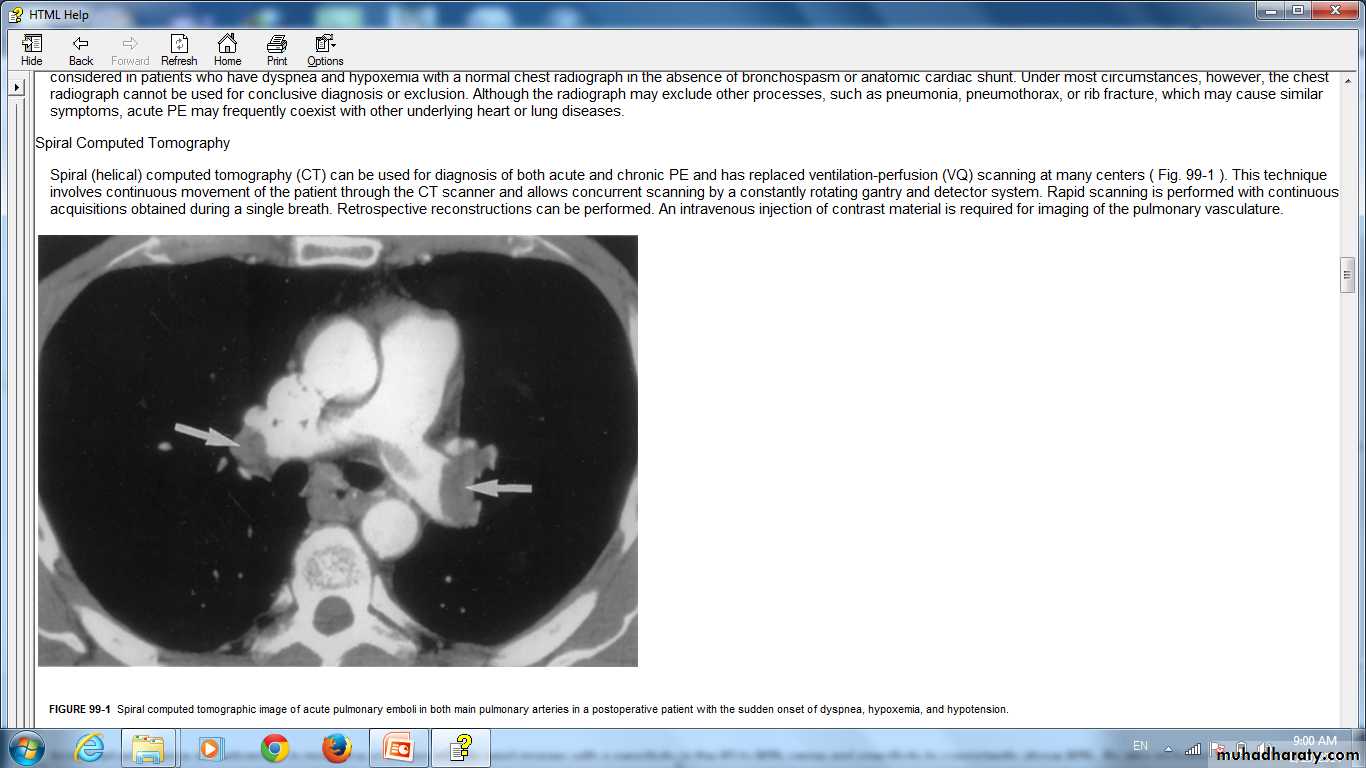

Spiral computed tomographic image of acute pulmonary emboli in both main pulmonary arteries in a postoperative patient with the sudden onset of dyspnea, hypoxemia, and hypotension.

CT

Helical CT pulmonary angiography sensitive and very specific.